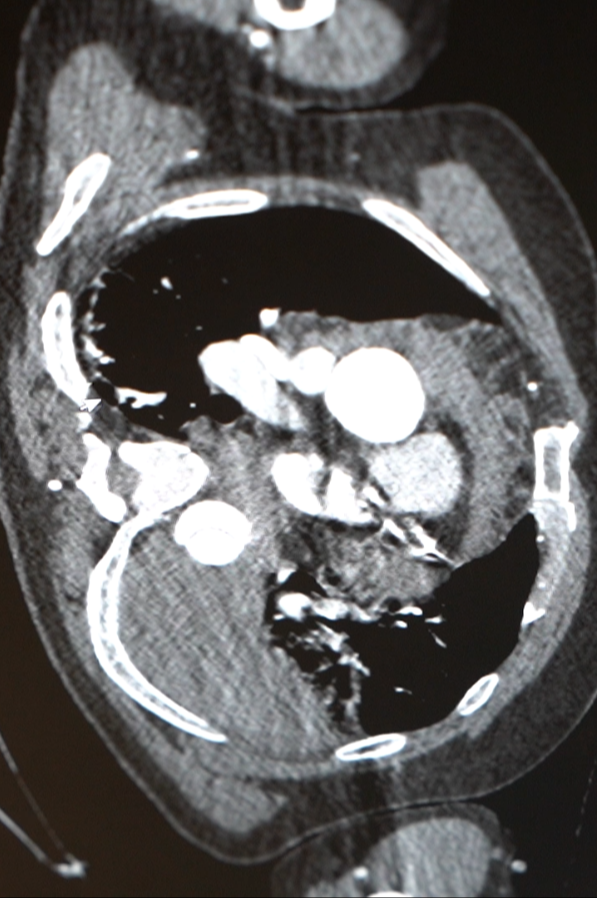

急诊检查结果不容乐观:胸腹主动脉夹层伴胸腔大量积液、纵膈积液——这些积液,考虑是从撕裂的主动脉里漏出来的!

医院心脏血管外科团队紧急会诊,这虽是B型主动脉夹层,但极其凶险,而且他已出现休克表现。“主动脉夹层就像水管壁分层开裂,一旦完全破裂,血液会瞬间涌入胸腔,没有任何抢救机会。他这种情况,已经是命悬一线。”心脏病院副院长张金洲语气凝重。